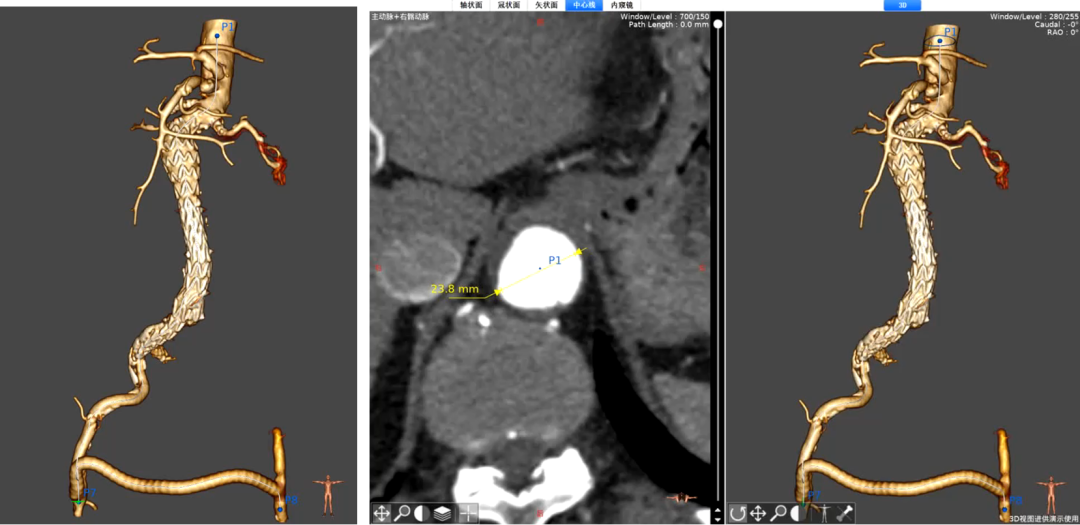

病例2:腹主动脉瘤合并双侧髂总动脉瘤

病情:患者男,86岁,腹主动脉瘤合并双侧髂总动脉瘤伴有腹主末端狭窄。

策略与操作

预处理:用球囊扩张腹主末端狭窄段,创造G-iliac™支架锚定空间。

右侧髂内动脉重建:植入G-iliac™支架,分支锚定至壁支远端,覆盖动脉瘤段。

左侧髂内动脉处理:因腹主支架进入后不适合 IBD 近端锚定长度,采用栓塞主干预。

左侧髂总动脉内腹主支架进入后不适合IBD近端长度,只能栓塞

随访结果

术后6月支架持续通畅,动脉瘤体缩小20%,无盆腔缺血症状。